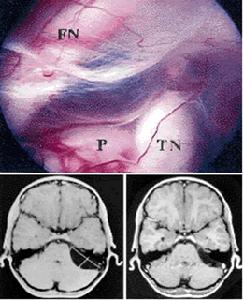

橋小腦角區囊腫內窺鏡切除術中所見1、好發於青少年患者;

2、可以沒有任何症狀,僅因頭痛、頭昏行CT、MRI檢查時發現;

3、常慢性起病,當外傷致蛛網膜囊腫囊內出血時,可突然起病;

4、腦積水由囊腫阻塞CSF循環引起,也可能與CSF吸收障礙有關,表現為顱內壓增高症狀;

5、囊腫壓迫局部腦組織可以出現癲癇、輕度運動和感覺障礙;

6、幼兒可出現頭顱增大和癱瘓;

7、CT或MRI可以確診;

8、CT或MRI增強可其它腫瘤相鑑別。